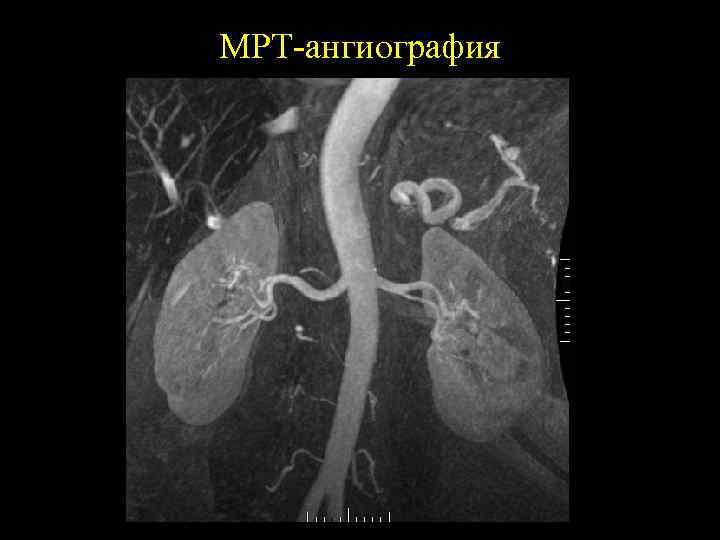

Почечные сосуды • Нативная МРТ позволяет получить изображеня сосудов

МРТ-ангиография

Преимущества МРТ • Высокое контрастное разрешение в изображении мягких тканей. • Возможность получения первичного изображения в различных плоскостях. • Отсутствие отрицательных биологических эффектов. • Хорошее контрастное разрешение. • Позволяет отчетливо увидеть сосудистые структуры без применения контрастных препаратов.